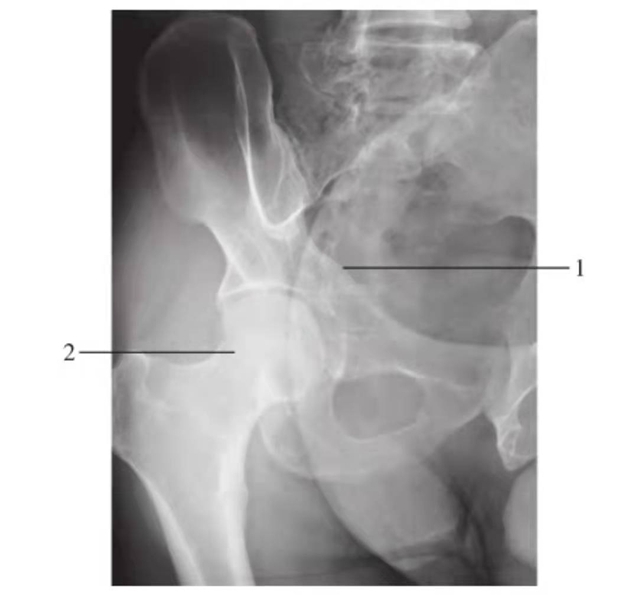

闭孔斜位

图9 右侧闭孔斜位

1.前柱;2.髋臼后唇

髂骨斜位

图10 右侧髂骨斜位

1.后柱;2.髋臼前唇